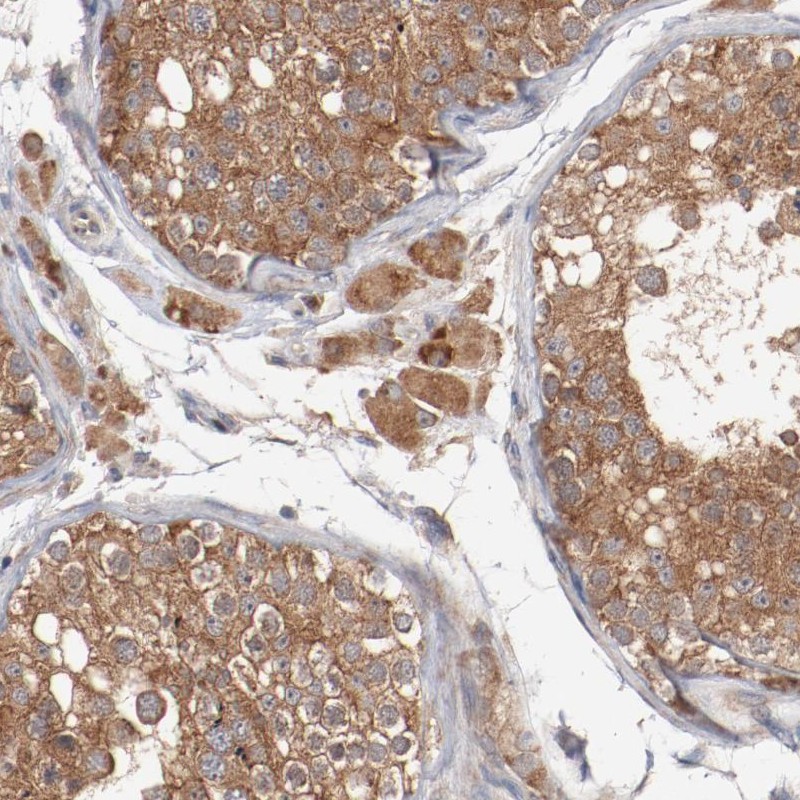

Immunohistochemical staining of human testis shows moderate cytoplasmic positivity in cells in seminiferous ducts and Leydig cells.